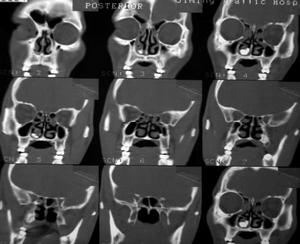

發生在骨盆、脊柱等部位的腫瘤,普通X光片不能很好地顯示時,CT掃描、B超、MRI、ECT等新型顯像技術可以幫助判明腫瘤的部位和範圍。

3、CT與核磁共振:能較早發現病變組織,準確率高。

圖緩釋庫療法的適應症

適應症:鼻咽癌、口腔癌、肺癌、食道癌、胃癌、腸癌;肝癌、膽囊癌、膽管癌、胰腺癌、腎癌、膀胱癌;子宮癌、卵巢癌、乳腺癌、前列腺癌、睪丸癌;甲狀腺癌、皮膚癌、惡性淋巴瘤、骨腫瘤、原發或轉移的各種實體腫瘤。